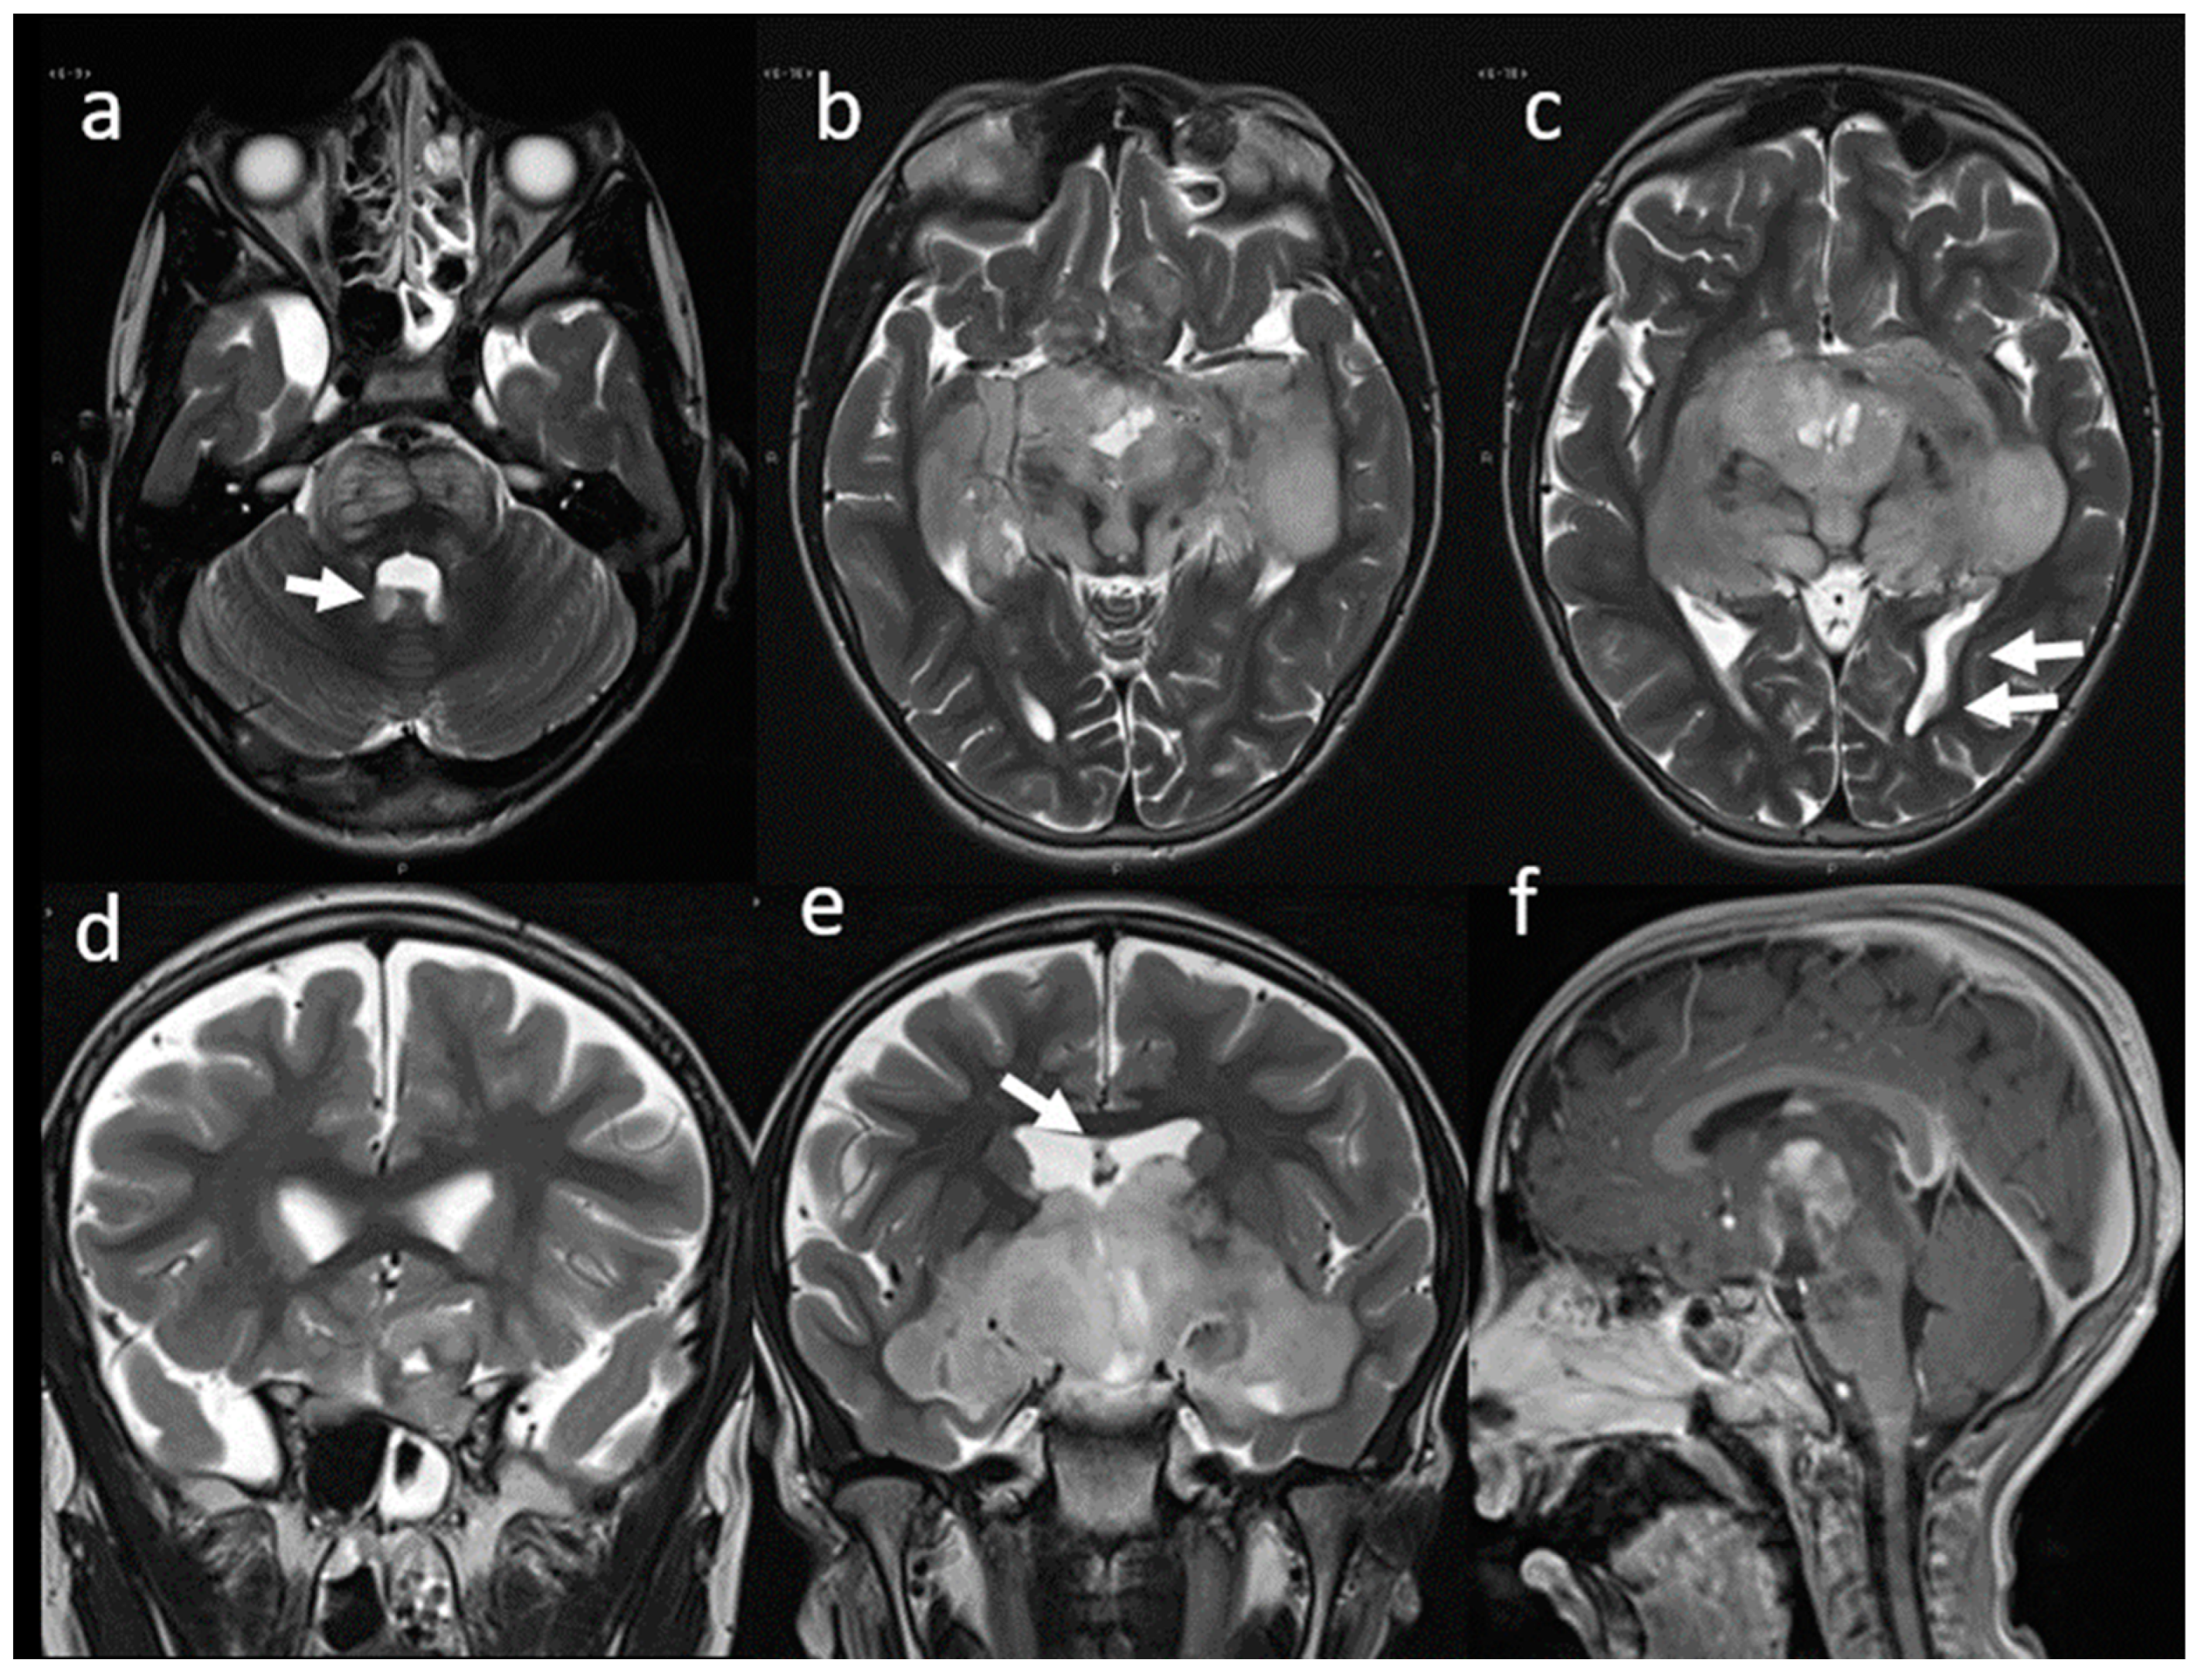

A magnetic resonance imaging (MRI) of the brain and spinal cord documented the presence of an infiltrative, space-occupying lesion involving the optic-chiasmatic region (Figure 1).

Figure 1. MRI. T2w axial (ac) and coronal (d,e) images show a large, heterogeneously hyper-intense, optic-chiasmatic lobulated mass with massive involvement of the optic nerves and tracts, optic radiations, hypothalamus, temporal lobes, and brainstem. The mass compresses the frontal lobes and extends into the third ventricle, resulting in moderate enlargement of the lateral ventricles. Sagittal Gd T1w (f) image shows inhomogeneous contrast-enhancement of the suprasellar mass.

Figure 2. MRI. T2w axial (ac) and coronal (d,e) images at the time of disease progression. Signal characteristics appear essentially unchanged. Multiple secondary localizations along the ventricular profiles are also well evident (arrows). Sagittal Gd T1w (f) image shows partial reduction of the inhomogeneous contrast enhancement of the suprasellar mass.